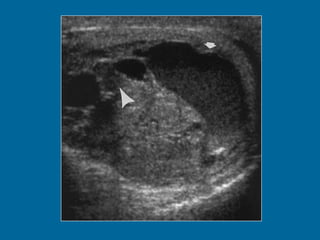

Intratesticular varicocele in a 38-year-old man.  (a) Transverse oblique US scan of left testis reveals multiple intratesticular anechoic cystic areas (arrowhead).  (b) Duplex Doppler US scan shows that venous flow in these cystic areas increases during a Valsalva maneuver (arrowhead).

Intratesticular varicocele ina 38-year-old man. (a) Transverse oblique US scan of left testis reveals multiple intratesticular anechoic cystic areas (arrowhead). (b) Duplex Doppler US scan shows that venous flow in these cystic areas increases during a Valsalva maneuver (arrowhead).